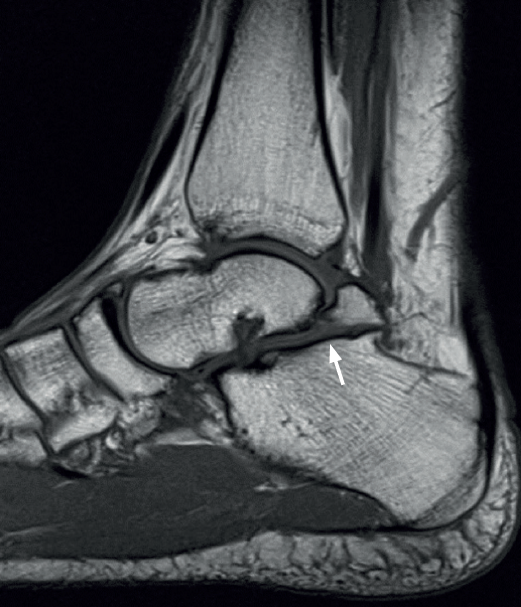

En su evolución suele presentar dolor, grados variables de afectación articular y edema óseo visible en los estudios por RM(10) que lleva a plantear tratamientos quirúrgicos en la serie de 4 casos de Rammelt et al.(58).

Hemos planteado en algunos de estos casos la artrodesis subastragalina por vía posterior, utilizando el propio osículo como autoinjerto (Figura 9), junto con artroscopia de tobillo por vía anterior sin resultados concluyentes por el momento y que precisan ser analizados a más largo plazo.